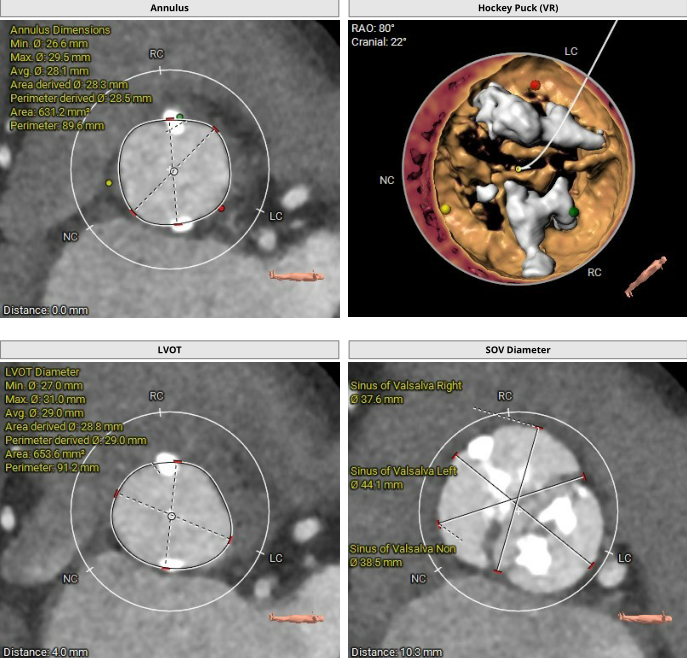

基于术前超声、CT及3D模型多模态影像分析,患者合并冠脉病变,未来需处理冠脉的可能性较大,采用长支架自膨瓣膜后期冠脉干预难度较大。同时,Type1型二叶瓣,且瓣环的两处明显团块钙化延伸至LVOT深度>5mm(12.3mm),长支架自膨瓣术后瓣周漏风险较高。综合考虑后拟选用Prizvalve球扩TAVR瓣膜,便于未来冠脉干预。此外,患者左冠开口平面可见瓣叶,瓣尖有较大团块钙化,左冠开口阻塞风险较大,拟行术中左冠保护。

针对瓣膜型号选择,根据主动脉瓣环面积631.1mm2折算直径28.3mm,LVOT29.0mm,按照常规标准需选择29mm PrizValve。因患者瓣叶为极重度钙化(Hu850钙化积分2322),瓣膜型号可适当downsize,应能较好在瓣膜位置锚定,也有利于减少冠脉开口阻塞风险。

综合评估后,拟采用右侧股动脉入路,25mm球囊预扩张、Balloon sizing并观察冠脉阻塞风险,左冠支架保护,26mmPrizvalve标准容量球囊扩张TAVR手术。